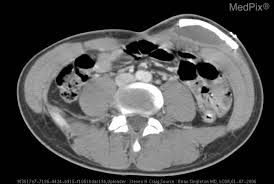

وفي محاولة لتجنب البتر، قرر الأطباء محاولة إنقاذ يد ماريوتي عن طريق وضعها جراحيًا في الأنسجة الرخوة في معدته.

ساعد الموضع على منع الإصابة بالعدوى والنخر، مع السماح للطرف بإعادة توصيل إمدادات الدم واستعادة العضلات والأنسجة.

"لم أقم بهذا الإجراء من قبل ولكني كنت أعرف ما هو ممكن. قال الدكتور بوريس برانداو من مستشفى مؤسسة سانتا أوتيليا: “لقد قمنا بفصل الجلد عن عضلات البطن وصنعنا كيسًا بداخله ووضعنا يد المريض بداخله”.